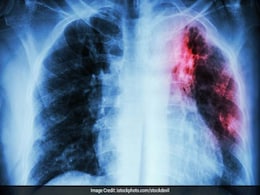

Tuberculosis Replaces Covid As Top Infectious Disease Killer, Says WHO

Tuberculosis replaced COVID-19 to become the top cause for infectious disease-related deaths in 2023, according to a World Health Organization report published on Tuesday, highlighting the challenges in the global effort to eradicate the disease.

Record 7.5 Million Diagnosed With Tuberculosis Globally In 2022: WHO

A total of 7.5 million people were diagnosed with tuberculosis in 2022, the highest recorded since WHO began global TB monitoring in 1995, according to a report featuring data from 192 countries and areas.

Tuberculosis Firmly On Rise, 14% Up Deaths In Last 2 Years: WHO

Tuberculosis has rebounded after years of decline, killing an estimated 1.6 million people in 2021, up 14 percent in two years, new World Health Organization figures showed Thursday.